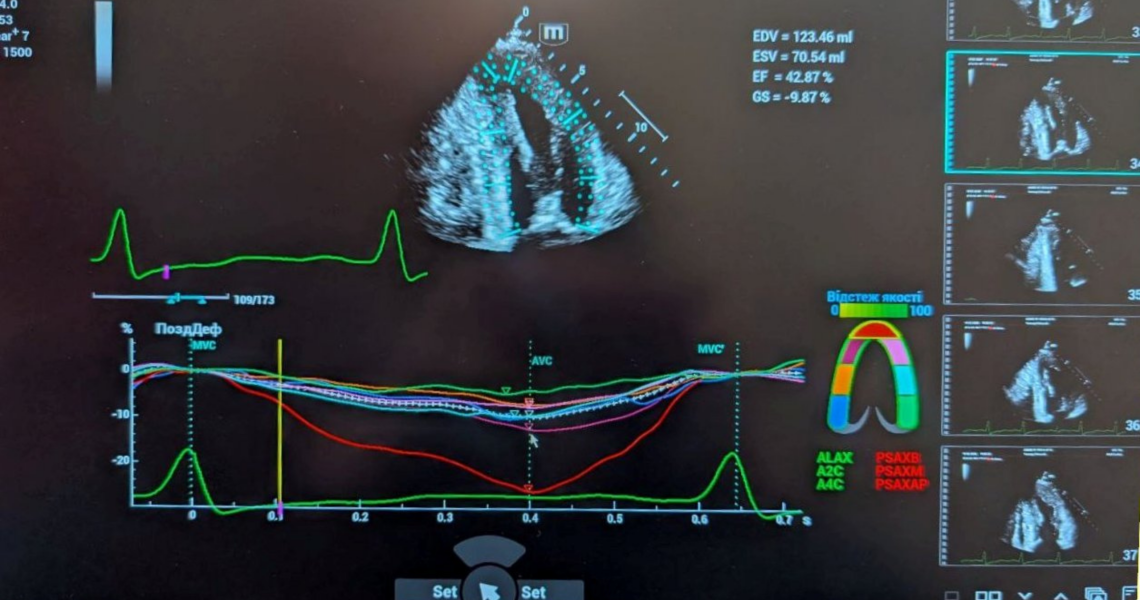

20 лютого 2026 року для співробітників кафедри пропедевтики внутрішньої медицини ПДМУ був проведений майстер-клас та практичний тренінг із клінічного застосування спекл-трекінг-ехокардіографії. Це сучасний, неінвазивний ультразвуковий метод, що дозволяє кількісно оцінити глобальну та регіональну скоротливість серця, виявити дисфункцію лівого шлуночка ще до появи клінічних симптомів або зниження фракції викиду, що надає можливість ранньої діагностики серцевої недостатності.

On February 20, 2026, a master class and practical training on the clinical application of speckle-tracking echocardiography was conducted for the staff of the Department of Propaedeutics of Internal Medicine at Poltava State Medical University. This state-of-the-art, non-invasive ultrasound method enables quantitative assessment of global and regional myocardial contractility, detection of left ventricular dysfunction even before the onset of clinical symptoms or a decrease in ejection fraction, thus allowing for the early diagnosis of heart failure.